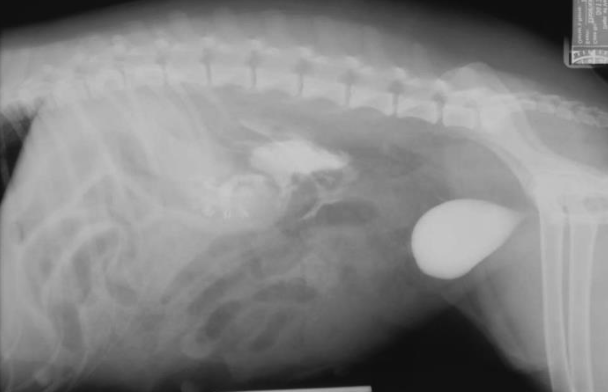

what is going on here?

one of the kidneys appears large and absnormally shaped, very circular, and there are small white opacities which are probably stones. this is hydronephrosis secondary to obstructive uropathy